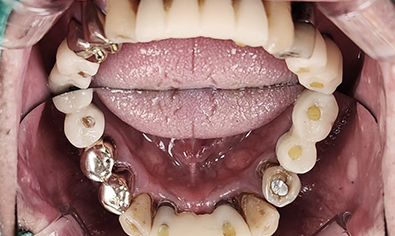

여러 원인으로 발생되는

임플란트 재수술

임플란트 환자 10명 중 1~2명은 재수술을 경험합니다.

임플란트는 시술 후 문제가 없다면

오래 사용할 수 있지만, 염증이나 부작용 등 다양한 요인으로 인해

재수술이 필요할 수 있습니다.

올디플란트치과는 정밀한 분석을 통해

근본적인 원인을 파악하고, 기존 임플란트를 살리거나 필요한 경우

재수술을 진행합니다.

문제 확인 및 검사

기존 임플란트 실패 원인을 파악하여 남아 있는 뼈 상태를 철저히 평가합니다.

뼈상태 평가 및 뼈이식고려

기존 임플란트 제거 후 뼈 이식을 진행하면 더욱 견고한 재수술이 가능합니다.

수술 및 예방관리

재수술 후 감염 가능성이 더 크기 때문에 철저한 예방관리가 이루어 집니다.